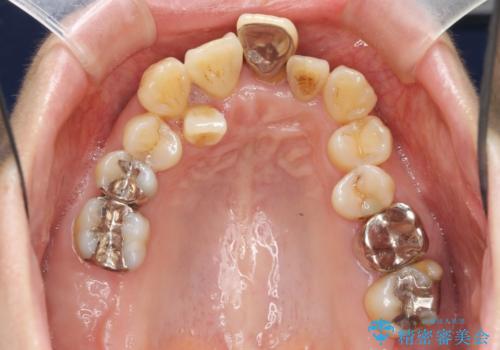

- 重度の歯周病に罹患しており、他院で「多数の歯を抜歯したのち、入れ歯を入れるしかない。」と言われ、入れ歯以外の方法がないか相談のため来院されました。

重度の歯周病で多数の歯を残せない問題、歯並び・噛み合わせの問題、欠損の問題、と多数の大きな問題が認められました。

このままの歯並びでは仮にインプラントを埋入したとしても歯ブラシがしづらく、また歯周病の問題が再発しやすい、と判断し矯正治療を行ったのちに歯周病治療、インプラント治療を行っていく治療計画としました。

インプラント治療に加え、歯周病に対しての再生治療や歯周ポケットの除去を行う歯周外科、矯正治療、と必要な治療は多岐に渡りましたが、最終的に安定した噛み合わせを得られたとともに、清掃のしやすい口腔内環境を確立できました。